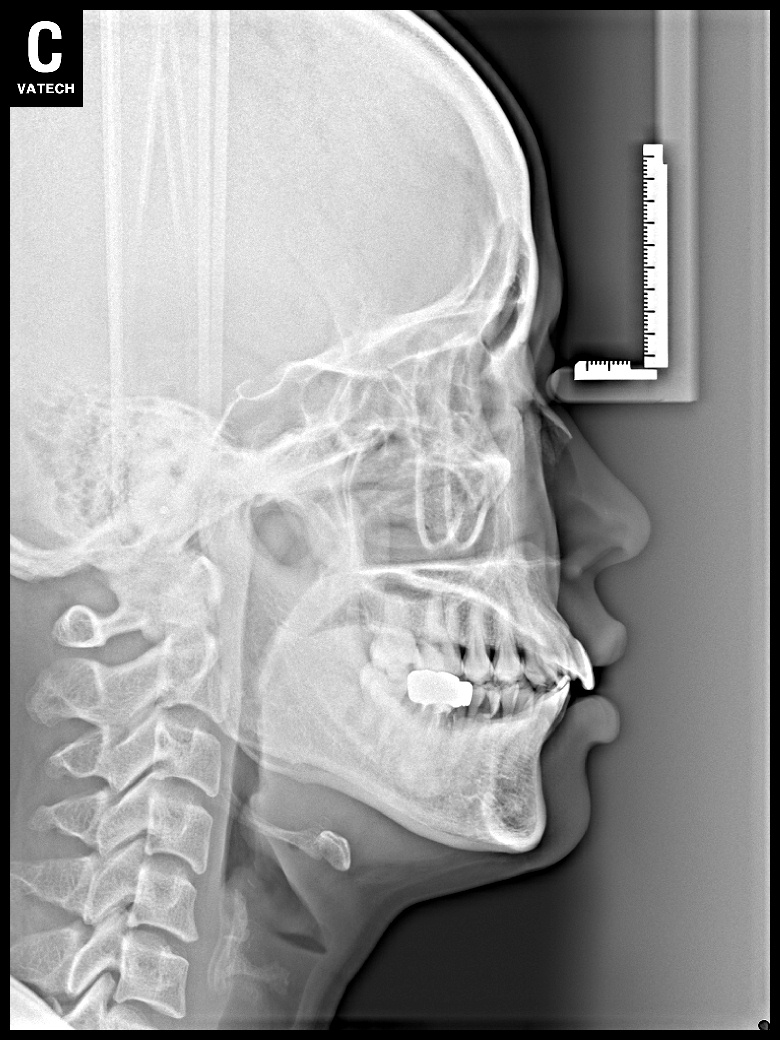

치료 후 사진입니다.